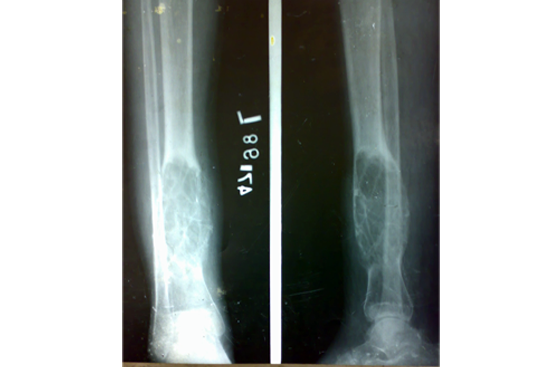

Tibialisation of Fibula

Method

We have done Huntington technique by stage ilizarov procedure. Here is the diagrammatic representation of our method.